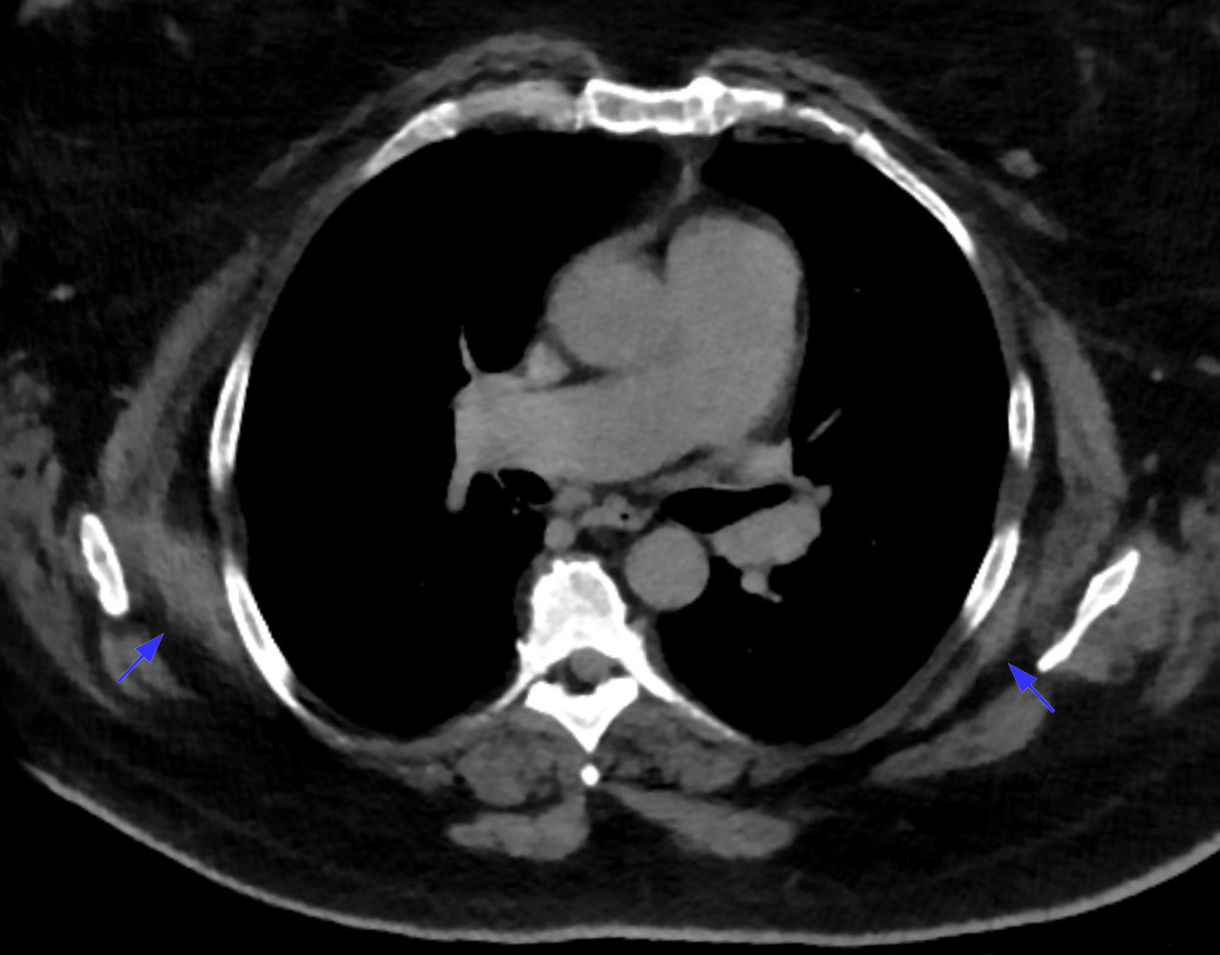

TC

- Masa lenticular entre escápula y pared torácica, con estrías lineales de densidad grasa intercaladas en tejido de densidad muscular.